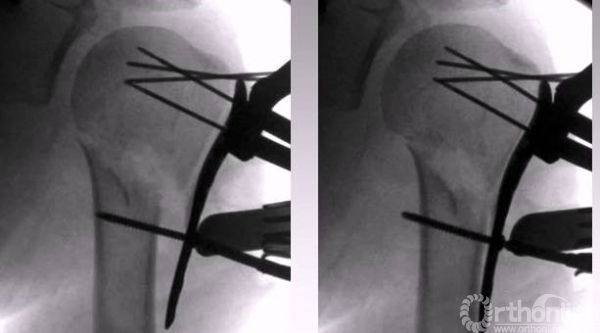

4.克氏针临时固定,用钢板压住骨折块。

1.克氏针摇杆技术;

以钢板进行复位,然后用皮质骨螺钉进行提拉 完成肱骨近端解剖形态。

解剖钢板与提拉螺钉的复位